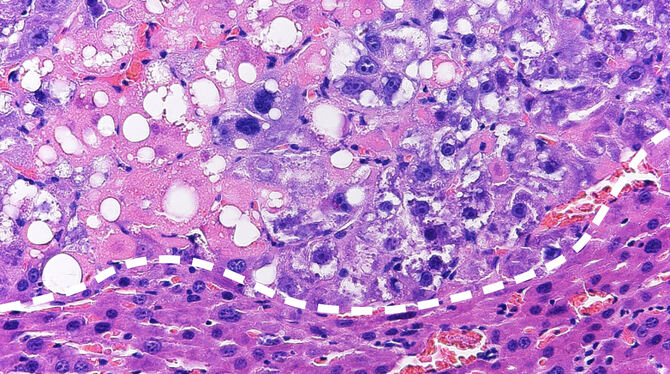

Beim neuen Ansatz wird therapeutisch in den Fettstoffwechsel der Tumorzellen eingegriffen. Durch Aktivierung des sogenannten LXR-Proteins kommt es zur Steigerung der Fettsäuresynthese. Diese kann zunächst von der Tumorzelle toleriert werden, weil anfallende gesättigte Fettsäuren (aus der Ernährungsmedizin auch als schlechte Fettsäuren bekannt) kontinuierlich durch ein Enzym zu ungesättigten (guten) Fettsäuren umgewandelt werden. Wird jedoch gleichzeitig ein zweites Protein, die sogenannte Raf-1 Kinase, gehemmt, so kommt es in der Tumorzelle zu einer Anreicherung von gesättigten Fettsäuren, welche von der Tumorzelle nicht toleriert werden kann und zum Zelltod der Tumorzelle führt. Von besonderer Bedeutung ist, dass das neue Therapiekonzept eine starke Wirksamkeit gegen Leberkrebs hat, welcher durch Leberverfettung (NASH) hervorgerufen wird. Klinische Studien haben gezeigt, dass diese sogenannten NASH-HCCs mit den derzeitigen zielgerichteten oder Immuntherapien nur schwer zu beherrschen sind.